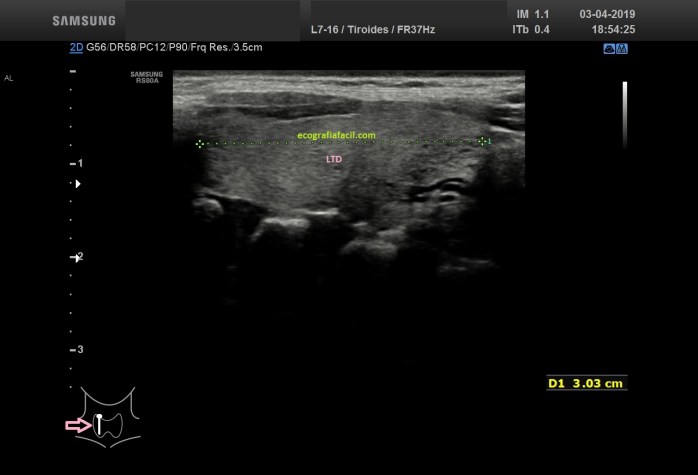

En la exploración habitual veremos la anatomía clásica representada en las figuras 1,2 y 3.

In the habitual exploration we will see the classic anatomy represented in figures 1, 2 and 3.